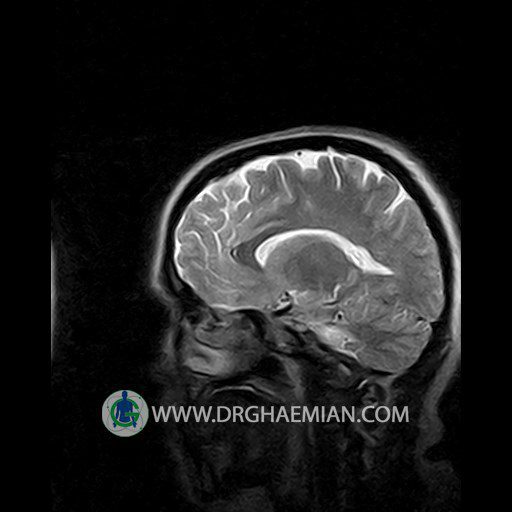

پزشکان اغلب از تصویربرداری ام آر آی برای تشخیص و درمان عارضه های پزشکی که فقط با استفاده از اشعه ایکس یا میدان مغناطیسی و امواج رادیویی قابل مشاهده است، استفاده می کنند. دستگاه ام آر آی تصاویر دقیق از ساختار های داخلی بدن ایجاد می کند. در این کیس نوریت اوربیت چب و سلای خالی بیمار مشاهده می شود.

Technique:Axial T1 , Axial , sagittal , coronal FSE T2 , coronal T1, sagittal fat sat T2 , Axial , sagittal T1 post Gd .

– Small fluid around the left optic nerve with mild edema suggestive for left optic neuritis

– Extension of suprasella cistern to sella with thin pituitary gland in floor of sella ( empty sella )

are seen